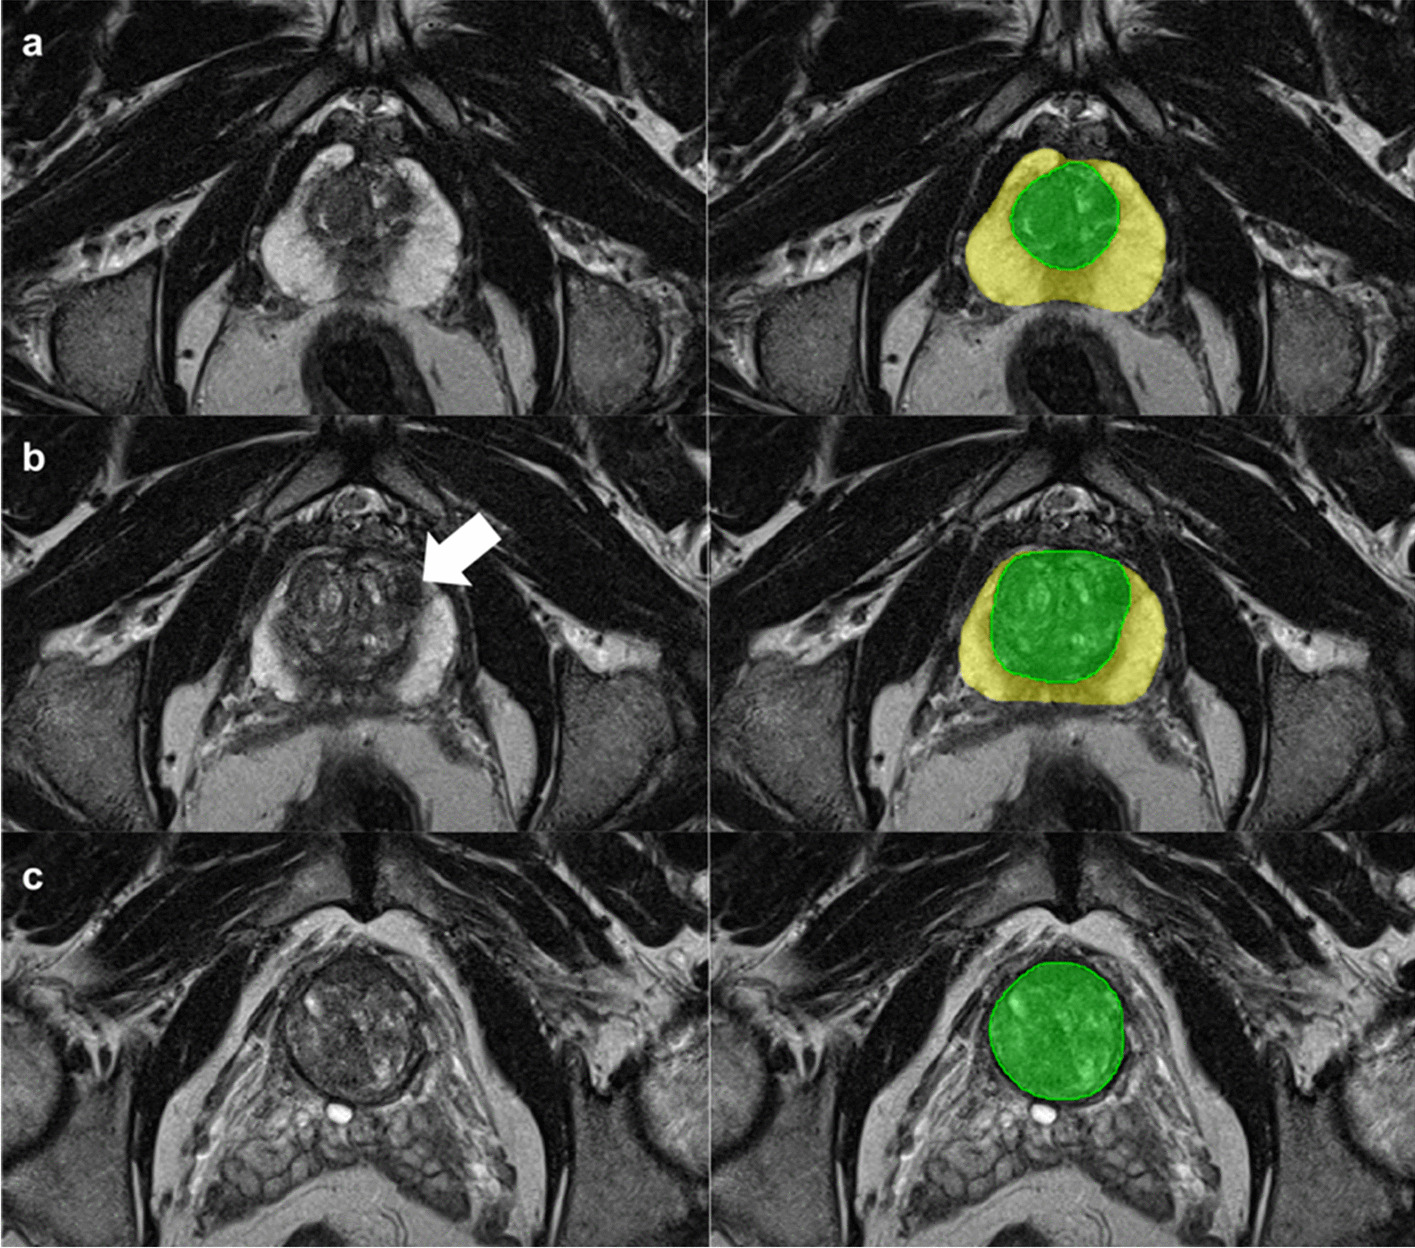

Fig. 2

Whole gland and transition zone segmentation at MRI using a nnU-Net. Axial T2-weighted images at three different levels of the prostate (left) and the correlating segmentation masks (right). The yellow and green masks represent the whole gland and transition zone volume, respectively. The white arrow indicates a target biopsy-proven Gleason Score 3+3 prostate cancer in the ventral transition zone

DL-based volume estimates had a segmentation DICE score of 0.89 (95%CI, 0.80–0.97) and 0.84 (0.70–0.99) for the WG and TZ at MRI, respectively, with a mean deviation of 4% from the manually segmented WG volume (2 mL of 50 mL WG; Fig. 2 and Supplementary Figures 1 and 2). The segmentation processing time was 12s (95%CI, 9–15s).